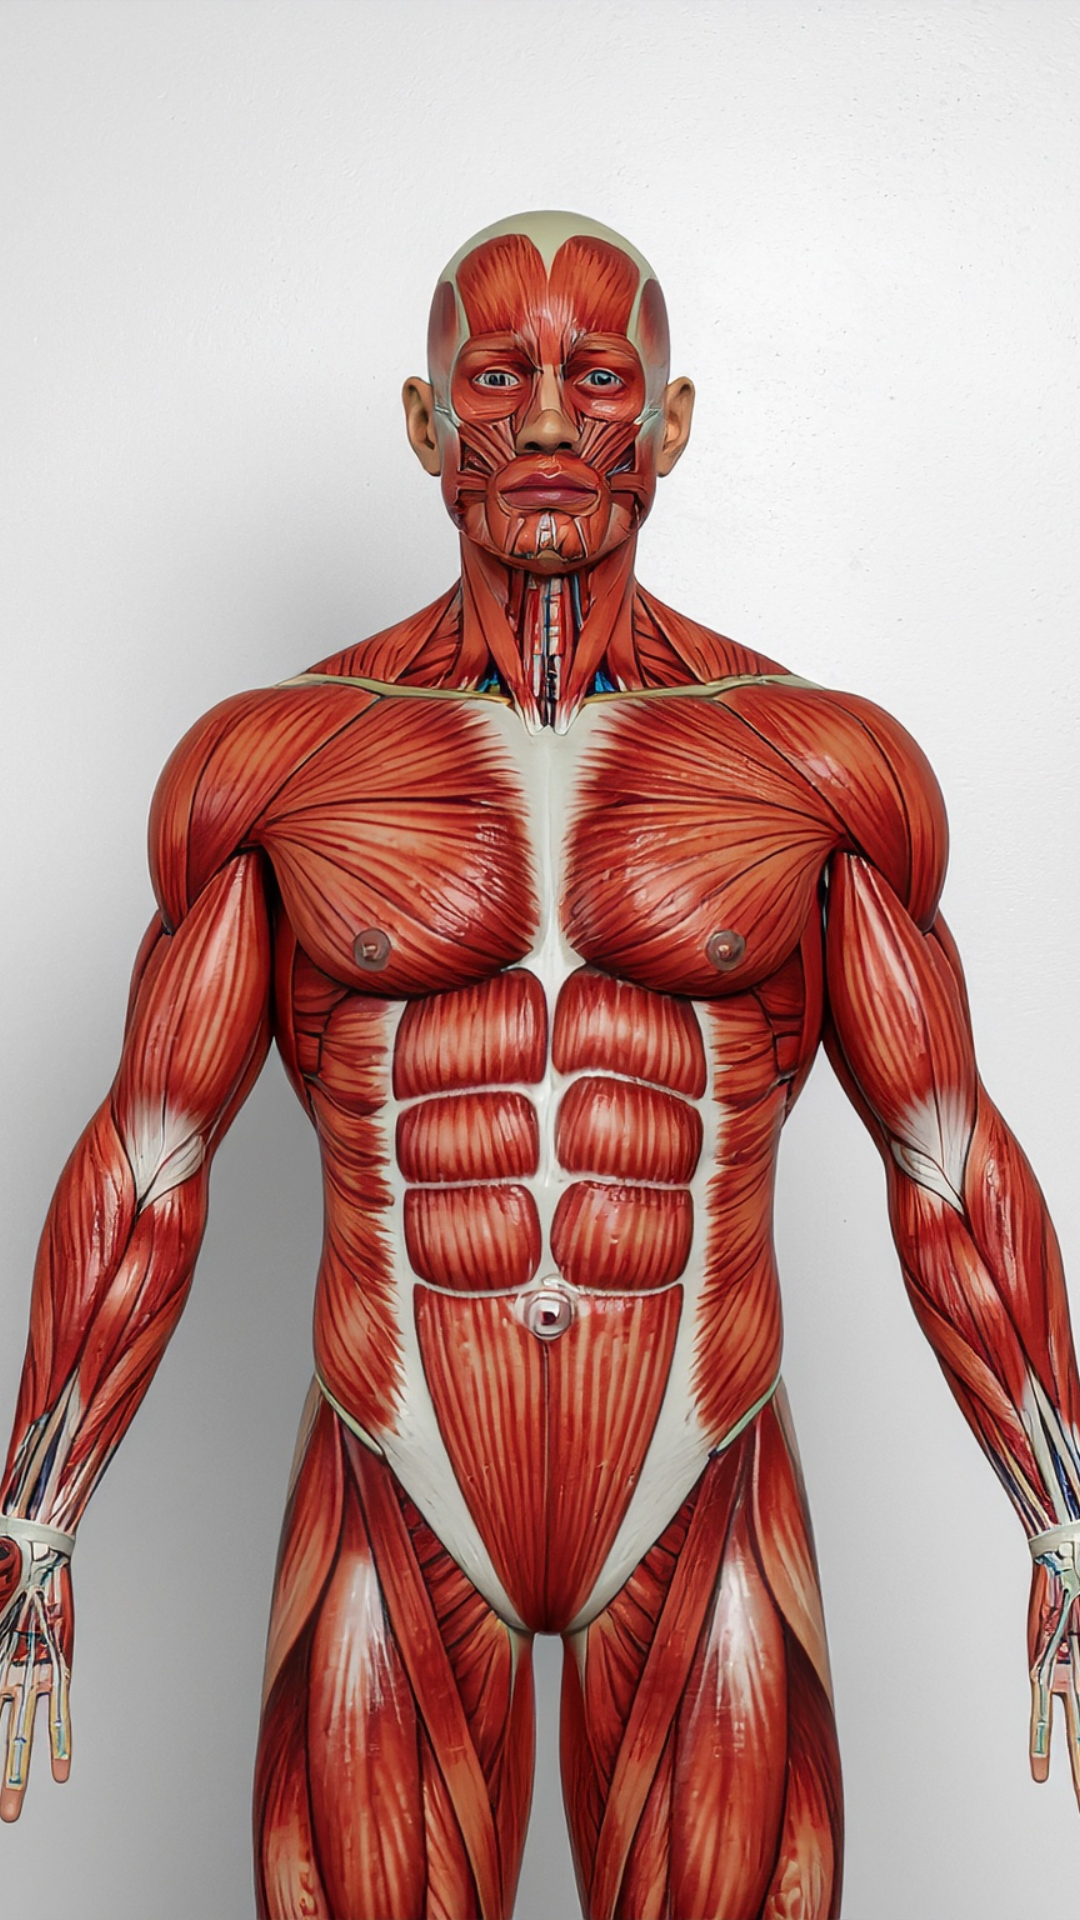

Somos una clínica especializada en la recuperación integral del movimiento y la mejora de tu calidad de vida, con tratamientos personalizados y enfoque humano.

Somos una clínica especializada en la recuperación integral del movimiento y la mejora de tu calidad de vida, con tratamientos personalizados y enfoque humano.

Acompañamos a cada paciente con compromiso, cercanía y enfoque humano durante todo su proceso de rehabilitación. Creemos en la recuperación integral: no solo del cuerpo, sino de la calidad de vida completa.

Evaluación y tratamiento terapéutico para mejorar el movimiento y aliviar el dolor.

Recuperación integral del movimiento con tratamiento personalizado y enfoque humano.

Rehabilitación especializada del sistema musculoesquelético en coordinación con ortopedistas.